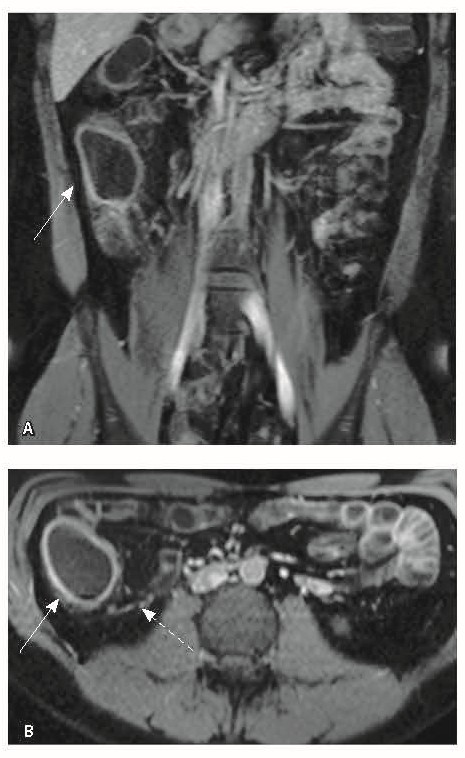

При мультиспиральной компьютерной томографии органов брюшной полости визуализировалась картина диффузного утолщения стенки толстой кишки с умеренным утолщением брыжейки и минимально выраженными явлениями лимфаденопатии в брыжейке (рис. 1).

Рис. 1. Мультиспиральная компьютерная томография органов брюшной полости с внутривенным введением контрастного вещества (йомепрол 350–100 мл), артериальная фаза: А – фронтальная проекция, Б – аксиальная проекция. Стрелками указано диффузное утолщение стенки толстой кишки и брыжейки